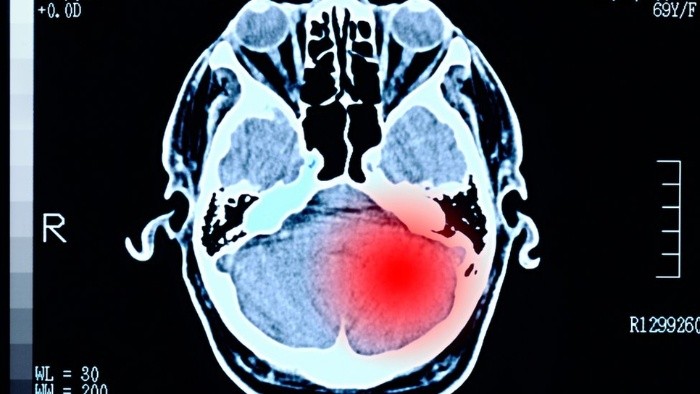

De acuerdo al profesor Stark, los tumores que representan un mayor reto para adolescentes y adultos jóvenes son los tumores cerebrales y los carcinomas, especialmente los alojados en el tracto digestivo.

"Los tumores cerebrales son un reto porque las posibilidades de tratamiento y los pronósticos de recuperación son extremadamente pobres", dice el especialista.

Según el Servicio Nacional de Salud británico (NHS), los tumores cerebrales pueden manifestarse con dolores de cabeza, convulsiones, mareos, naúseas recurrentes, problemas de memoria, cambios de personalidad, debilidad y parálisis progresivas en una parte del cuerpo y problemas de visión o habla.